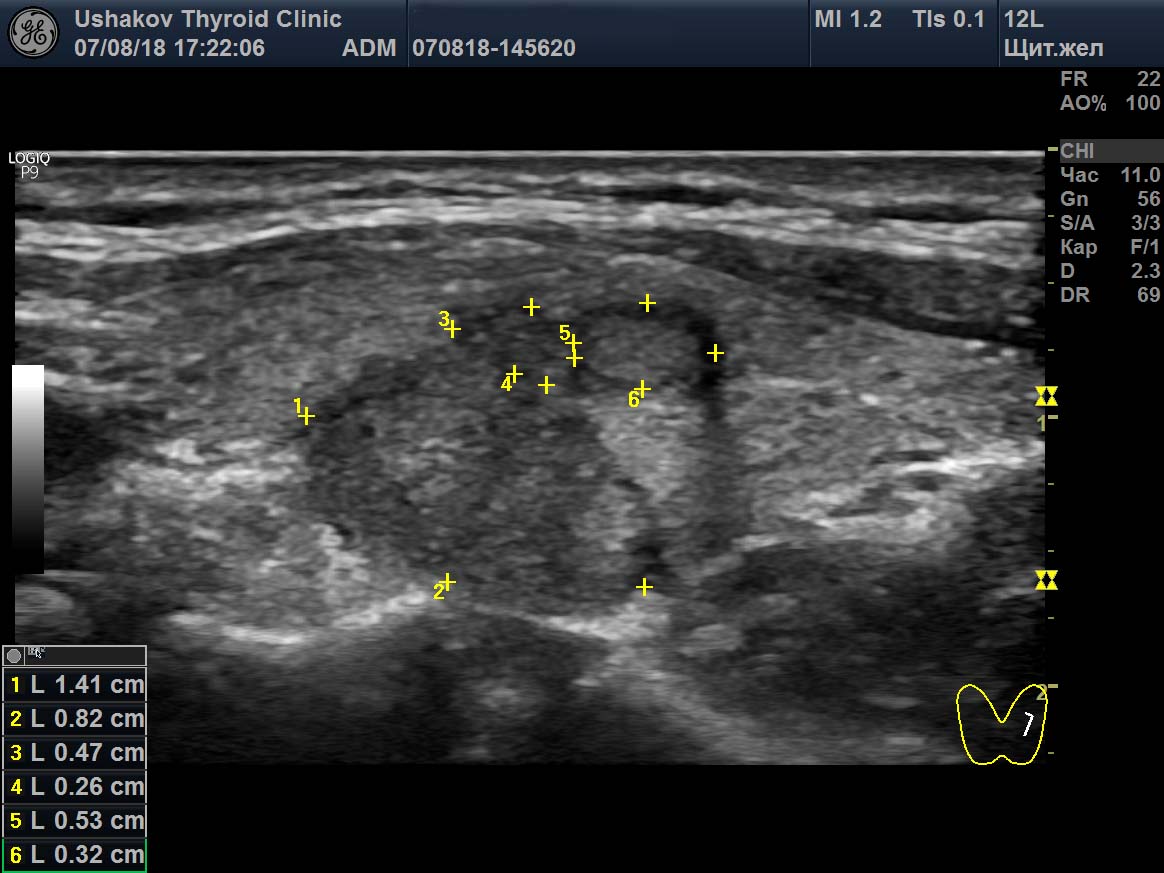

Узи щитовидной калининград

Узи щитовидной калининград 108 фотографий